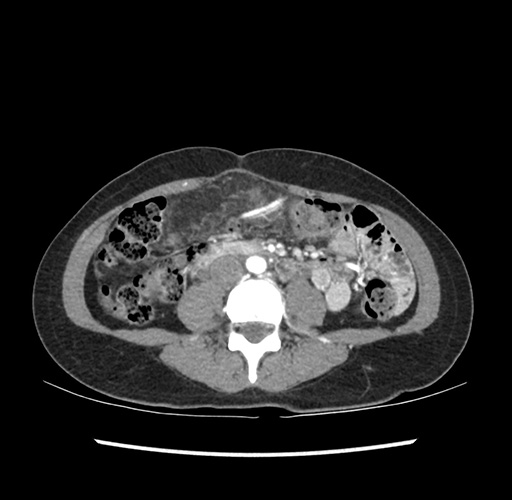

Imaging Analysis

Look through the patient's CT scan to identify any areas of concern for the necessary procedure.

Based on your CT findings, which issue(s) would give reason for "planned slowing down moment(s)" in this case?

Considering a standard left lateral sectionectomy procedure, what step(s) of the operation would you do differently in this case ?